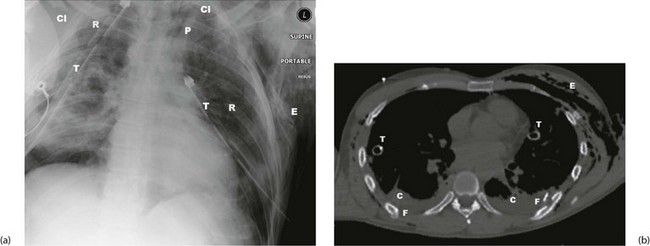

X-rays and other investigations: In major trauma, the cervical spine (see below, Fig. 15.10), chest and pelvis are X-rayed in the resuscitation room. The chest films must be good enough to exclude major chest wall, mediastinal and lung injuries and provide a baseline if the patient later deteriorates. Polytrauma patients, or patients with serious head injury should have rapid assessment and stabilisation before swift transfer for trauma CT scan. Patients should not be moved to the CT scanner until they are stable—the machine is known as the ‘donut of death’ in ATLS parlance.

| Rupture of bronchus (uncommon) | Respiratory distress, surgical emphysema in the neck; suggested by air in mediastinum on chest X-ray (see Fig. 15.9a); confirmed by bronchoscopy | Operation by thoracic trained surgeon |

Chest injuries are a common cause of death in patients with multiple injuries, although the death rate has fallen dramatically wherever seatbelt wearing is compulsory. Seatbelts, however, often cause typical sash pattern bruising obliquely across the chest, and minor rib and sternal fractures (Fig. 15.8). Serious chest injuries may be present without external injury, particularly tearing of mediastinal contents (aorta, bronchi and oesophagus). Diagnosis goes hand in hand with urgent resuscitation. Good-quality chest X-rays (or CT scans) are essential and usually reveal the diagnosis (see Fig. 15.9).